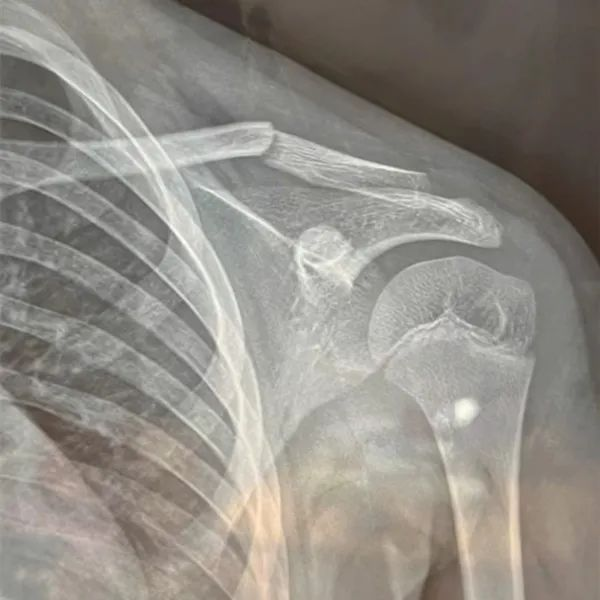

事故导致孩子左侧锁骨中外段骨折